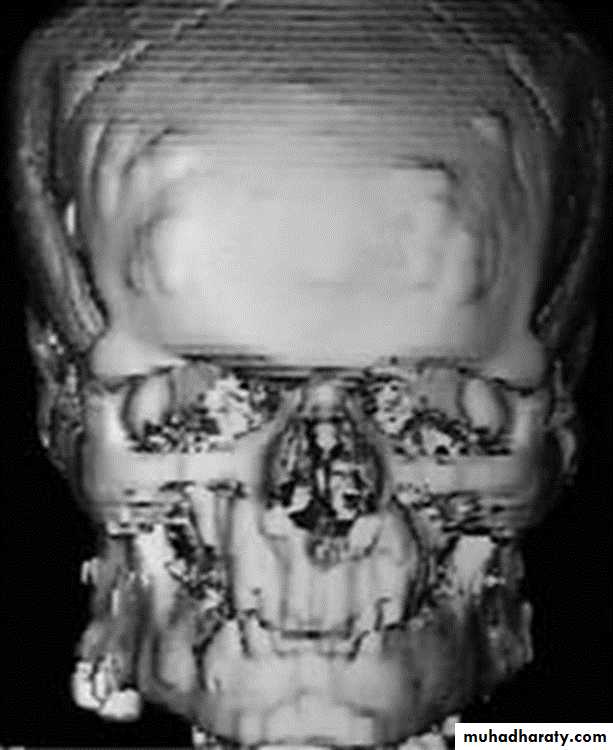

1- Abnormality in complex bones as the spine, pelvis, face and skull.

3- 3D is useful in planning corrective surgery for fracture & bone deformity.